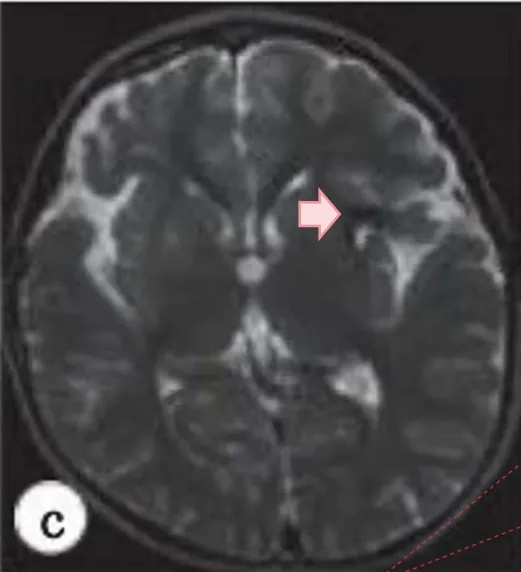

然而一个月后再行检查,发现病变已经扩大并压迫了周围的脑组织(图4a–c).尽管病变无症状,但预计病变还会进一步扩大,产生神经症状;经过商议,因此决定采用显微手术切除病变。

INC国际烟雾病大家川岛明次教授主刀下,利用原有手术入路,保留直接旁路,打开额、颞叶的硬脑膜以保存中脑膜动脉,显微镜下暴露、识别旧血肿,术中未发现任何动脉瘤或血管异常,血肿被完全清除。术后桃子恢复良好,无后遗症。术后一年核磁复查显示术前血肿消失。

在我们的病例中,在血管重建手术半年复查DSA显示烟雾血管消退(图2),但发现血肿扩大后重复DSA显示基底神经节毛细血管再增生。实际上,CD34/EVG染色的病理标本显示有大量的微血管。